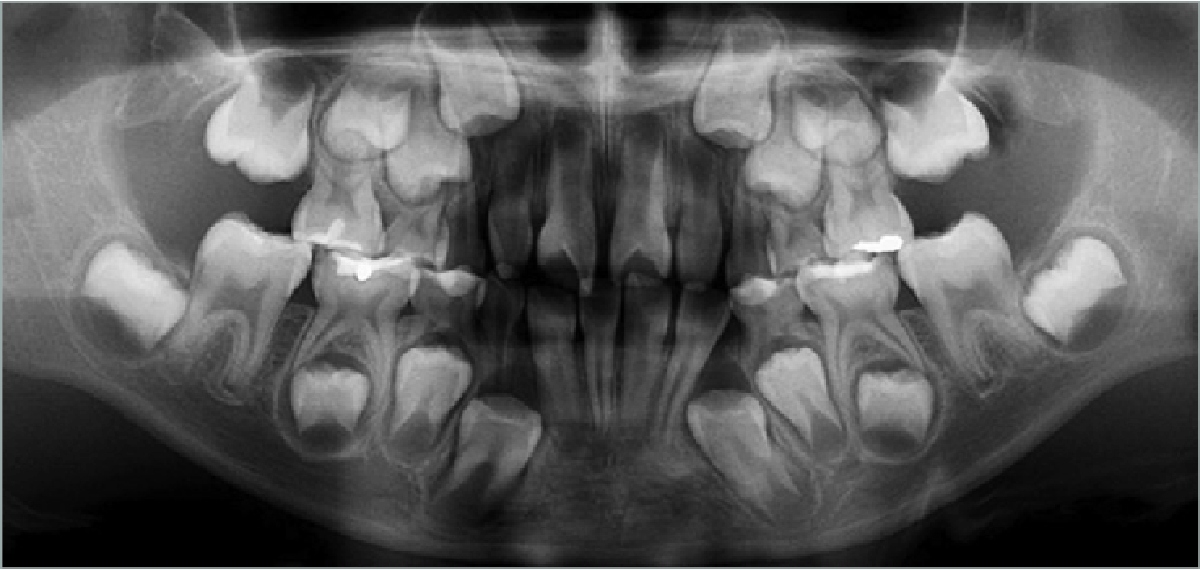

സൂപ്പര് ന്യൂമറ്റി പല്ലുകള് അതായത് അധിക പല്ലുകളുണ്ടാവുക. സാധാരണയേക്കാള് കൂടുതലായി പല്ലുകളുടെ എണ്ണം ഉണ്ടാകുന്ന അപൂര്വ്വ ദന്തവൈകല്യമാണ് മള്ട്ടിപ്പിള് ഹൈപ്പര് ഡോണ്ടിയ. മനുഷ്യനില് 32 പല്ലുകളാണ് ഉള്ളത്. ഹൈപ്പര്ഡോണ്ടിയ ഉള്ളവരില് ഡസണ് കണക്കിന് പല്ലുകള് ഉണ്ടാകുന്നുണ്ട്. സാധാരണ ഈ അവസ്ഥയുള്ള ആളുകളില് ഒന്നോ രണ്ടോ അധിക പല്ലുകള് മാത്രമേ ഉണ്ടാകാറുളളൂ. എന്നാല് മള്ട്ടിപ്പിള് ഹൈപ്പര് ഡോണ്ടിയയില് വായുടെ ഒരു വശത്തോ ഇരുവശങ്ങളിലോ ഒറ്റയ്ക്കോ കൂട്ടമായോ പല്ലുകള് വളരുന്നു.

ഈ 11 വയസ്സുകാരി പെണ്കുട്ടിക്ക് പെട്ടെന്ന് ചികിത്സ നല്കുന്നത് എളുപ്പമുള്ള കാര്യമായിരുന്നില്ലെന്നും ശസ്ത്രക്രിയ വിദഗ്ധരും ദന്തിസ്റ്റുകളുടെയും കൂട്ടായ ആലോചന പ്രകാരം ഒന്നിലധികം ശസ്ത്രക്രിയയിലൂടെ പല്ലുകള് നീക്കം ചെയ്യുകയും പെണ്കുട്ടിയുടെ സ്വാഭാവിക സംസാര ശേഷിയും ചവയ്ക്കാനുളള കഴിവും വീണ്ടെടുക്കുകയുമായിരുന്നു ഡോക്ടര്മാരുടെ ലക്ഷ്യം.